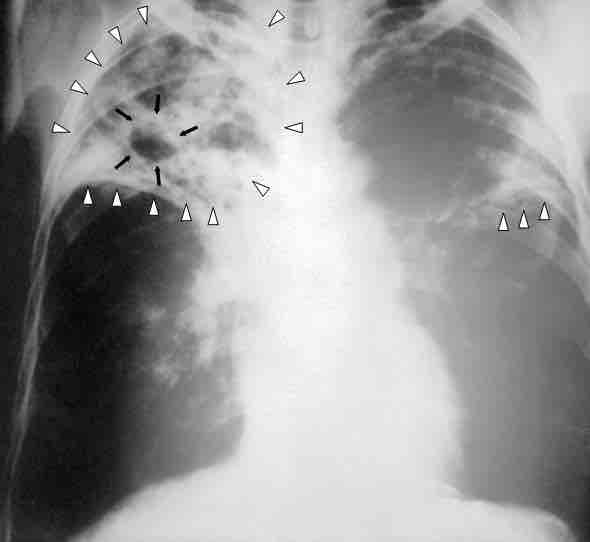

Chest x-ray of a patient with tuberculosis.

In this chest X-ray of a person with advanced tuberculosis, the infections in both lungs are marked by white arrowheads and the formation of a cavity is marked by black arrows. The boundary between contagious and non-contagious infectious diseases is not perfectly drawn, as illustrated by tuberculosis, which is clearly transmissible from person to person, but was not classically considered a contagious disease.